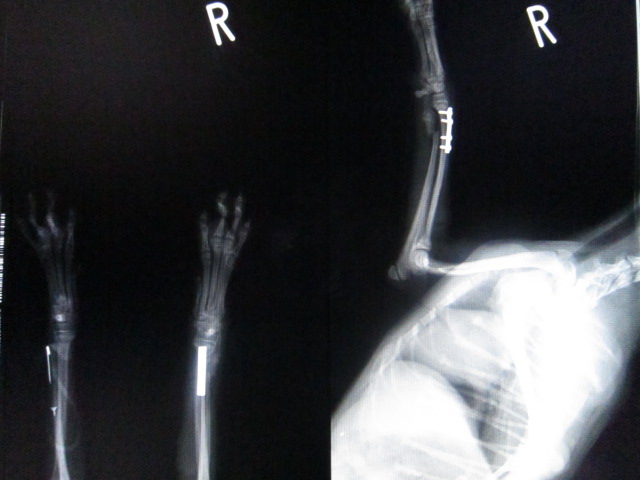

術後のレントゲンです。

プレートで固定致しました。